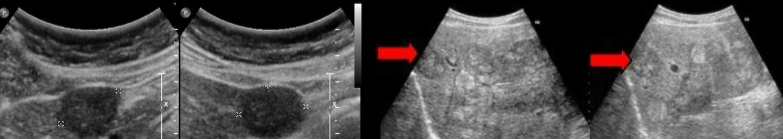

metastasis

lymphoma